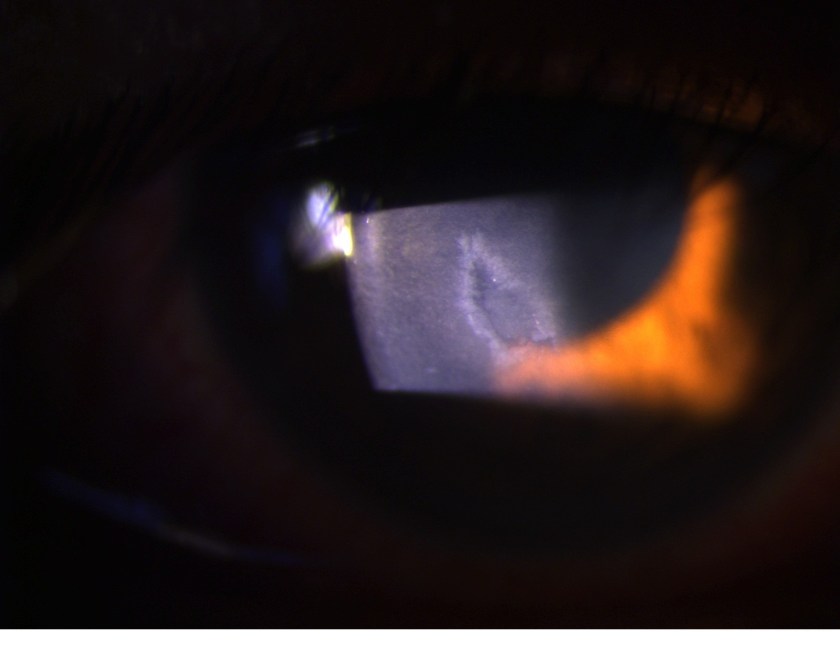

Imagine the skin of the eye getting an abrasion like your knee. This can happen from relatively trivial trauma, like a scratch from your fingernail or being brushed by a tree branch. The cornea is the surface layer of the eye and it has a skin layer similar to the skin on our bodies, but has 5 times the number of pain receptors per square mm compared to the skin on your body. For that reason, cornea abrasions are exquisitely painful.

Unlike the skin on your body, which heals completely relatively quickly, the skin on your cornea takes a long time to heal completely. New cells grow over to cover the abrasion in a matter of days, but these cells are immature and don’t stick well to each other. It takes a period of months to years for these cells to mature and stick firmly to each other. In the meantime, patients are at risk for recurrent cornea erosions.

When the cells are immature, minor trauma can cause the sheet of cells to detach from the cornea, and the patient sustains a cornea abrasion all over again. Sometimes the trauma is nothing more than the patient opening his eyes in the morning- the movement of the eyelid over the immature sheet of cornea cells is enough to cause the abrasion to happen!